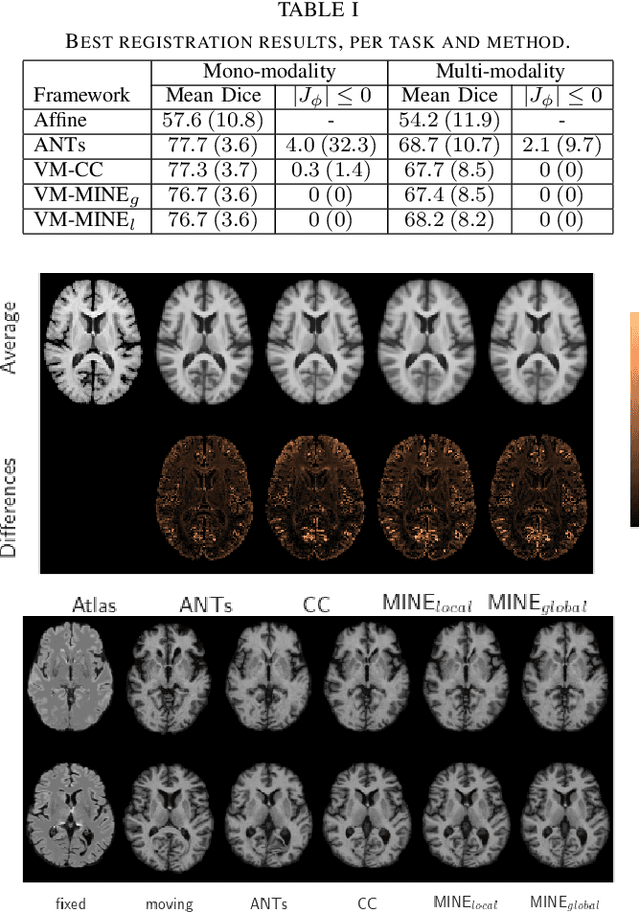

Abstract:Many applications in image-guided surgery and therapy require fast and reliable non-linear, multi-modal image registration. Recently proposed unsupervised deep learning-based registration methods have demonstrated superior performance compared to iterative methods in just a fraction of the time. Most of the learning-based methods have focused on mono-modal image registration. The extension to multi-modal registration depends on the use of an appropriate similarity function, such as the mutual information (MI). We propose guiding the training of a deep learning-based registration method with MI estimation between an image-pair in an end-to-end trainable network. Our results show that a small, 2-layer network produces competitive results in both mono- and multimodal registration, with sub-second run-times. Comparisons to both iterative and deep learning-based methods show that our MI-based method produces topologically and qualitatively superior results with an extremely low rate of non-diffeomorphic transformations. Real-time clinical application will benefit from a better visual matching of anatomical structures and less registration failures/outliers.